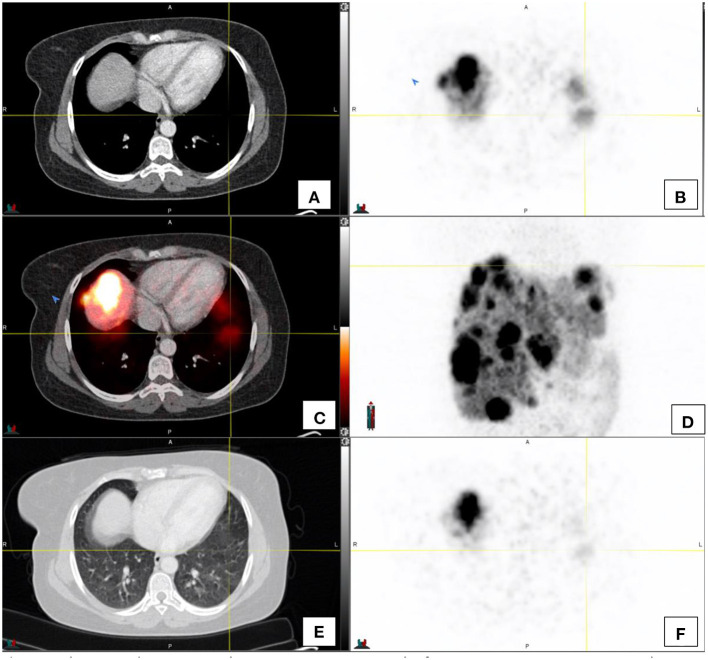

三十多年来,Indium 111 DTPA Octreotide(Octreoscan)一直是核医学生长抑素受体(SSTR)成像的支柱。PET/CT的出现带来了生长抑素的新类似物,由于其标记用于正电子成像的镓68,因此具有更高的亲和力和改进的分辨率。最常用的类似物包括DOTATATE、DOTATOC和DOTANOC。然而,镓68–1,4,7,10-四氮杂环十二烷-1,4,7,10-四乙酸(DOTA)-奥曲酸(DOTATE)可能是最常见的非FDG(氟-2-脱氧葡萄糖)PET示踪剂,与PSMA(前列腺特异性膜抗原)并列。与F18标记的FDG相比,由于Ga68发生器的可用性,它不需要接近回旋加速器。DOTATATE是一种生长抑素类似物,可以对细胞表面的生长抑素受体进行全身成像。68Ga-DOTA化合物为高分化(1级和低2级)神经内分泌肿瘤(NETs)提供了成像标准,并用于NETs患者的分期、表征和再分期。68Ga-DOTATE与18F-FDG具有互补作用,其中肿瘤可能表现出不同程度的分化。此外,它还可作为治疗的前奏,用于选择使用治疗方法进行肽受体放射性核素治疗的患者。对放射性示踪剂的正常生物分布有充分的了解,对于最佳的患者结果和避免潜在的假阳性(如炎症、正常的胰腺钩突摄取和成骨细胞活性)至关重要。在这篇综述中,我们将在图像的支持下描述68Ga-DOTATE的正常外观和潜在的陷阱,以帮助改进对这一关键创新工具的解释,从而管理表达SSTR的肿瘤个体。

Indium 111 DTPA Octreotide (Octreoscan) has been the pillar of Somatostatin receptor (SSTRs) imaging in nuclear medicine for over three decades. The advent of PET/CT brought new analogs of somatostatin that have higher affinity and improved resolution due to their labeling to Gallium 68 for positron imaging. The most used analogs include DOTATATE, DOTATOC and DOTANOC. However, Gallium 68-1,4,7,10-tetraazacyclododecane-1,4,7,10-tetraacetic acid (DOTA)-octreotate (DOTATATE) is probably the most common non-FDG (fluoro-2-deoxy glucose) PET tracer alongside PSMA (prostate specific membrane antigen). In contrast to F18-labeled FDG, it does not require proximity to a cyclotron due to the availability of the Ga68 generator. DOTATATE is a somatostatin analog which allows whole body imaging of somatostatin receptors on cell surfaces. 68Ga-DOTA compounds provide the imaging standard for well-differentiated (Grade 1 and low grade 2) neuro-endocrine tumors (NETs) and is utilized in the staging and characterization and restaging of patients with NETs. 68Ga DOTATATE has a complementary role with 18F-FDG where tumors may exhibit varying degrees of differentiation. It furthermore has application as a prelude to therapy in selecting patients for peptide receptor radionuclide therapy using a theranostic approach. A sound knowledge of the normal biodistribution of the radiotracer is imperative for optimal patient outcome and to avoid potential false positives such as inflammation, normal pancreatic uncinate process uptake and osteoblastic activity. In this review, we will describe the normal appearances of the 68Ga DOTATATE and the potential pitfalls with the support of images to aid in improving interpretation of this crucial innovative tool in the management of individuals with tumors expressing SSTRs.